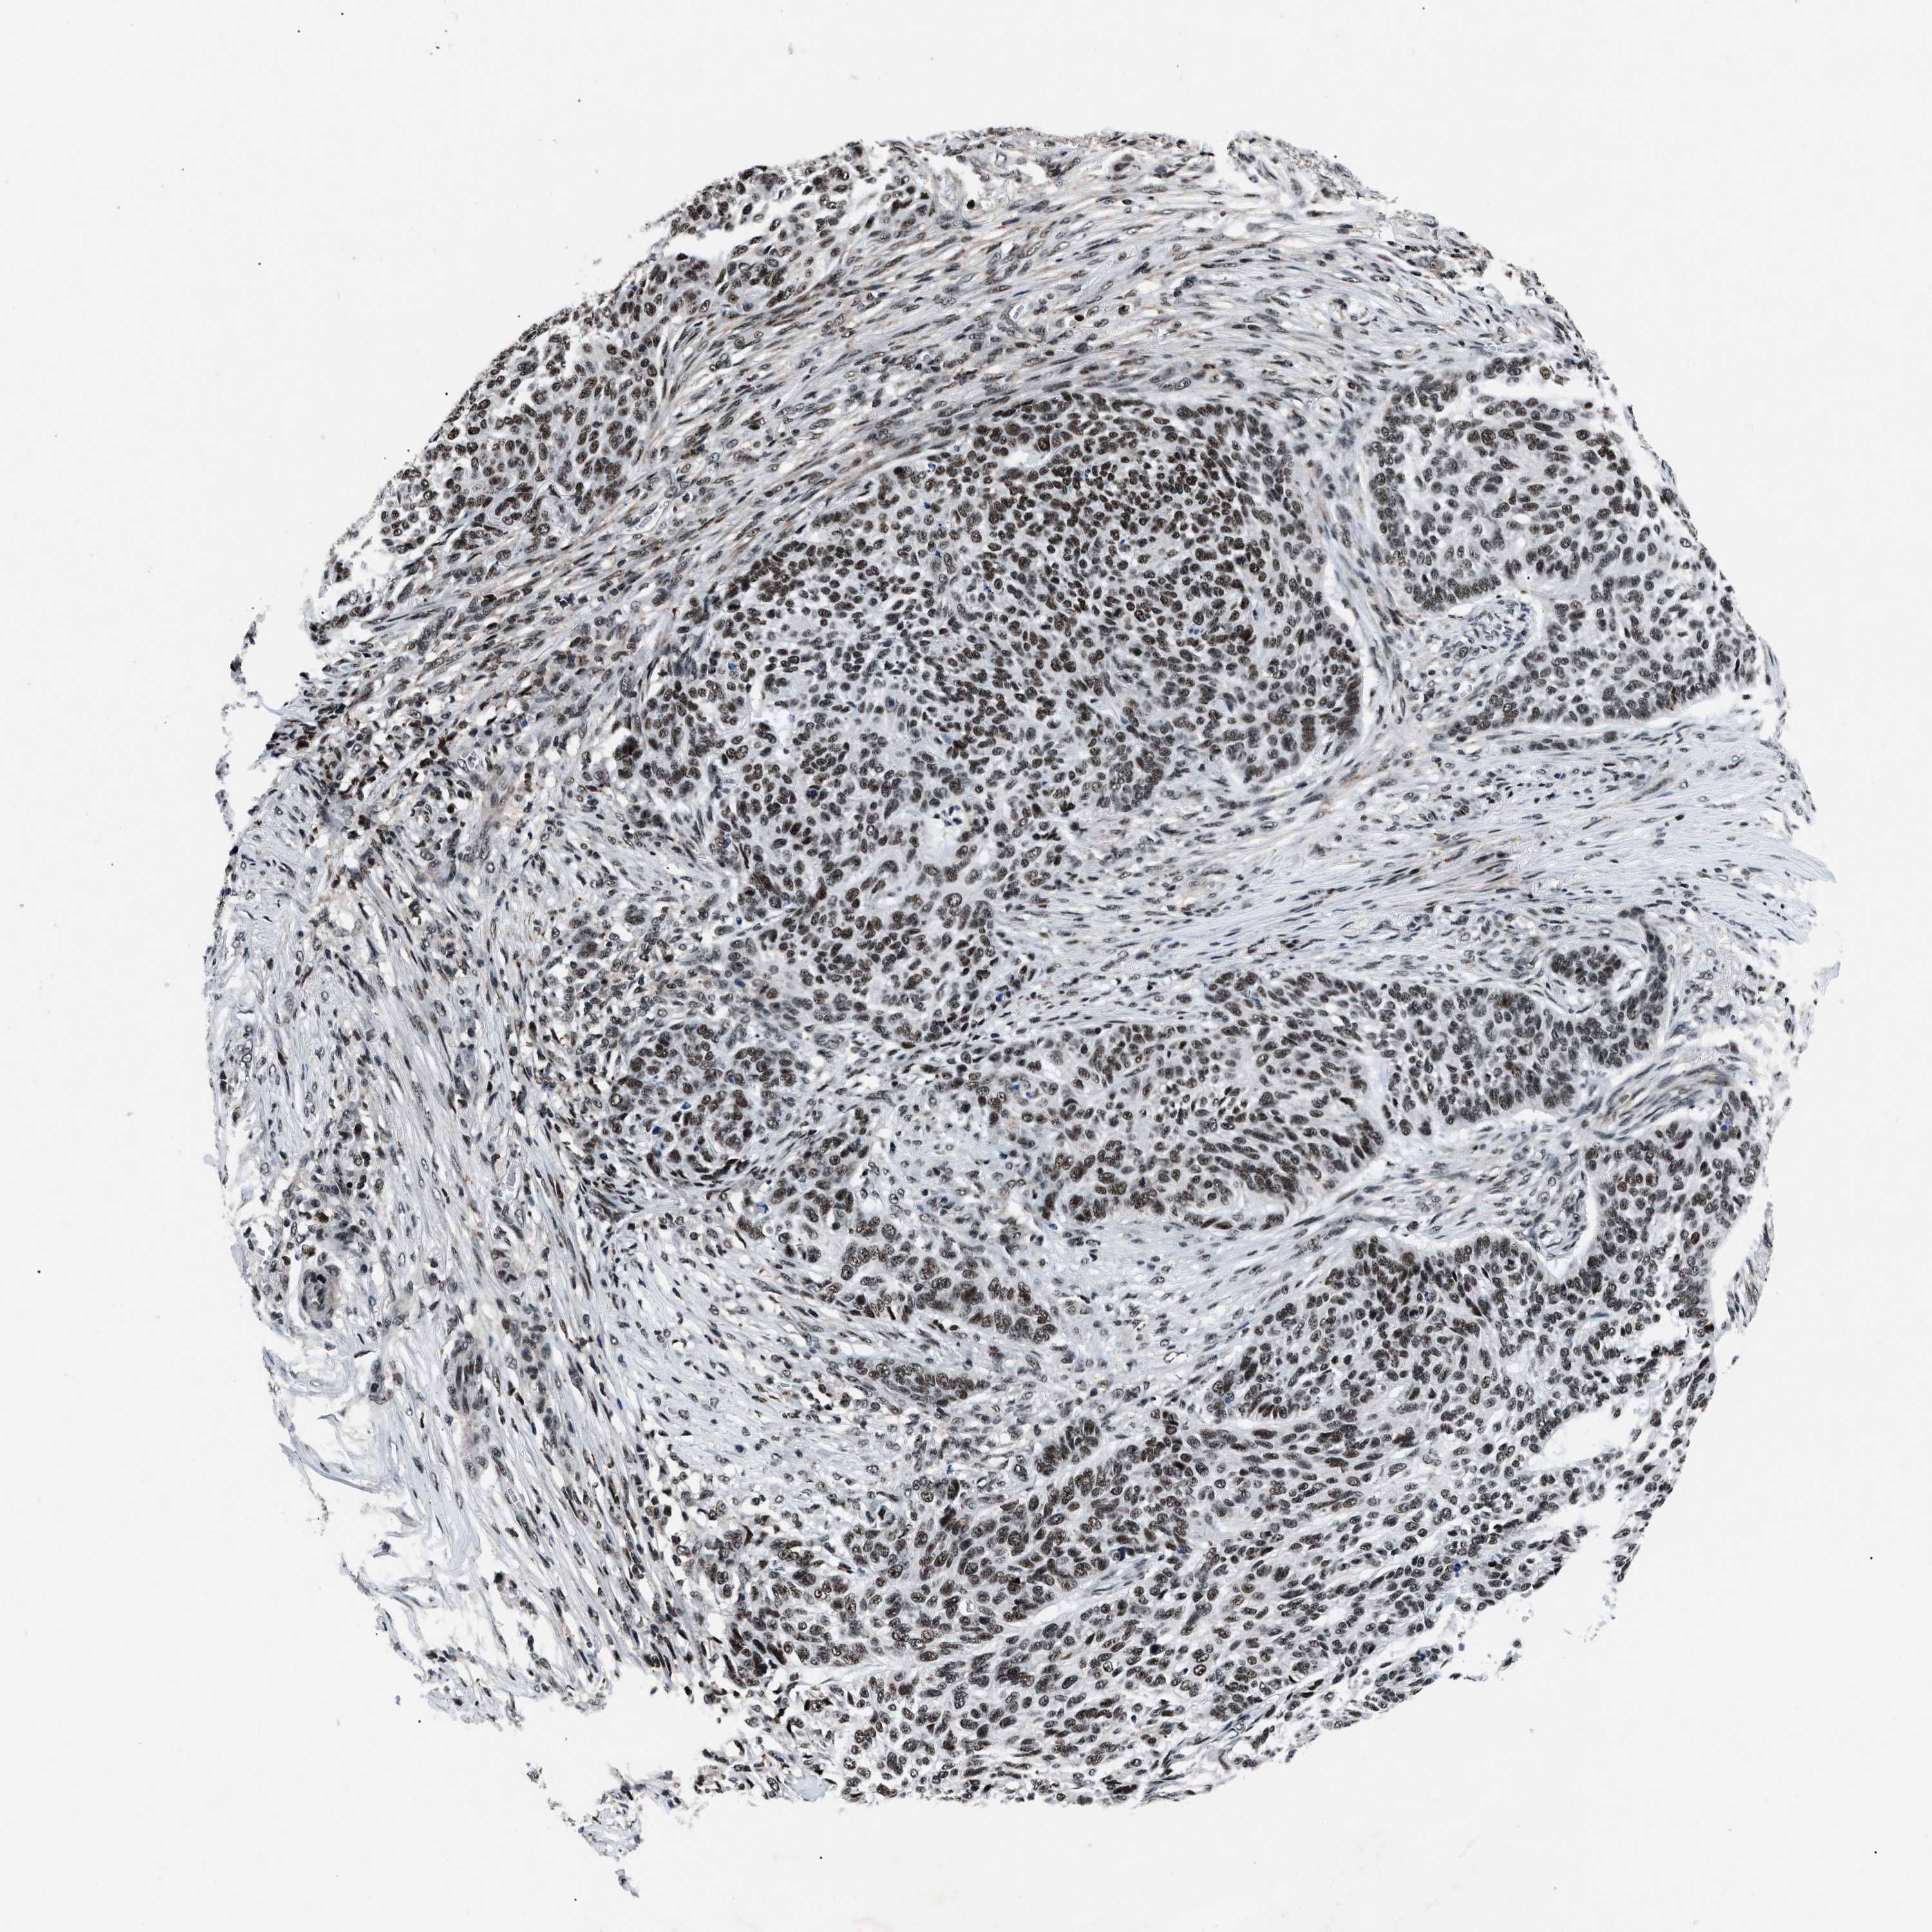

SKIN CANCER - Protein expressioni

A mouse-over function shows sample information and annotation data. Click on an image to view it in a full screen mode. Samples can be filtered based on level of antibody staining by selecting one or several of the following categories: high, medium, low and not detected. The assay and annotation is described here.

Antibody staining in the annotated cell types in the current human tissue is reported as not detected, low, medium, or high, based on conventional immunohistochemistry profiling in selected tissues. This score is based on the combination of the staining intensity and fraction of stained cells.

Each image is clickable and will lead to virtual microscopy that enables deeper exploration of all samples and also displays staining intensity scores, fraction scores and subcellular localization as well as patient and tissue information for each sample.

Antibody HPA018248

Staining

High

Strong

>75%

Location

Squamous cell carcinoma, NOS